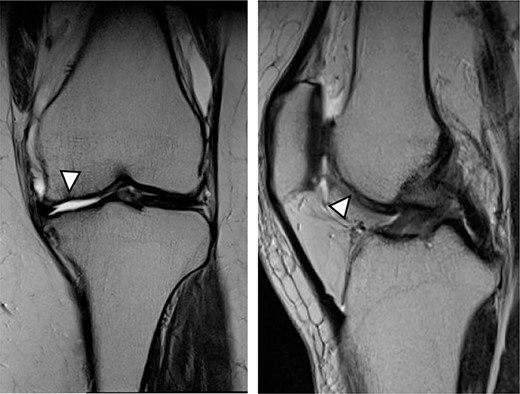

There were cartilage defects (arrowhead) in the medial femoral condyle and trochlea of the left knee (a, b).

A 42-year-old female (BMI, 27.4 kg/m2) presented with 2 years of left knee medial joint pain. Active range of motion (ROM) in the left knee was from 0 to 140 degrees with no extension lag. Preoperative Tegner scores, Lysholm scores and Knee Injury and Osteoarthritis Outcome (KOOS) scores are shown in Table 1. Preoperative radiographs of the left knee joint showed mild medial osteoarthritis (OA) of the knee and hip–knee–ankle (HKA) angle of 1.5-degree varus. 1.5-Tesla MRI was performed on unit (Toshiba, Kawasaki, Japan) was used with an extremity surface coil. Proton density images were obtained using the fast spin-echo technique. A modified magnetic resonance observation of cartilage repair tissue (MOCART) system was used for the quantitative evaluation of MRI findings of the cartilage injury [15–17]. MRI showed cartilage injury of the medial femoral condyle (MFC) and trochlea of the left knee (Fig. 1).

MRI showed cartilage injury of the medial femoral condyle (arrowhead).